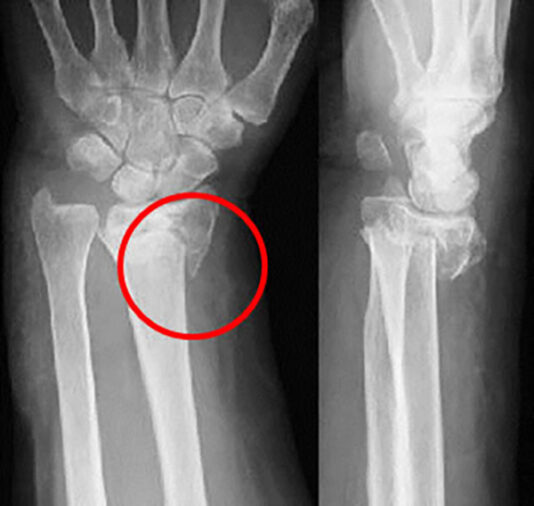

下の図の赤丸の部分になります。

橈骨茎状突起骨折は、橈骨遠位端骨折の一種で、橈骨茎状突起に斜めに骨折線が入った骨折型です。

診断は、レントゲンで骨折や転位の有無を確認します。

下のレントゲン写真では、橈骨茎状突起に斜めに骨折線が入り、骨折していることがわかります。